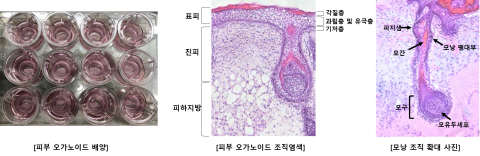

강스템바이오, LG전자와 피부 오가노이드 기반 미용기기 평가 나서

강스템바이오텍은 최근 LG전자와 피부 오가노이드 모델을 통해 미용기기의 효능평가를 진행했다고 24일 밝혔다. 회사는 기존 피부 오가노이드의 한계점을 극복해 신뢰도 높은 새로운 평가방식을 제시했으며, 해당 연구는 P&K피부임상연구센타를 통해 대한화장품학회 학술대회에서 발표했다고 전했다. LG전자는 미용기기 효능에 대한 기전 등 과학적 근거를 확보하고자 강스템바이오텍의 피부 오가노이드를 적용한 효능평가를 요청했다. 이에 강